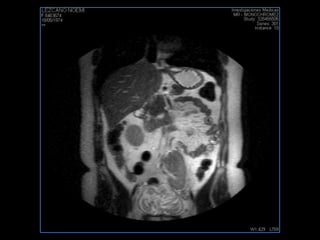

LIC ALEJANDRA GALVEZ RM DE ABDOMEN

resonancia de abdomen